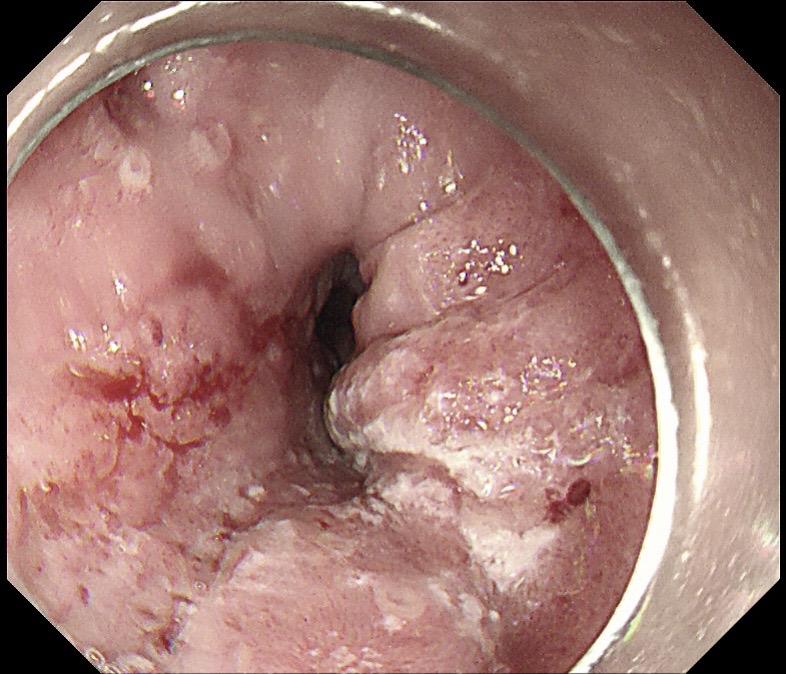

老年人吞咽不畅必有妖!老年人被鲍鱼卡住,做胃镜之前就怀疑是不好的病,胃镜把鲍鱼取出来后一看果然是!